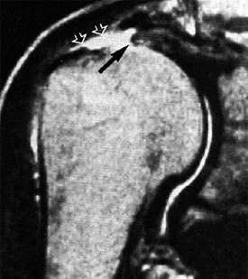

These two MRI images at right show the head of the humerus with the rotator cuff lying on top of it. The cuff is typically dark in color. The bright white-ish spots (see arrows) are showing the "gap" that occurs when the rotator cuff tears and separates. In general, the greater the gap, the more the tissue has retracted back and the more potentially difficult the repair.